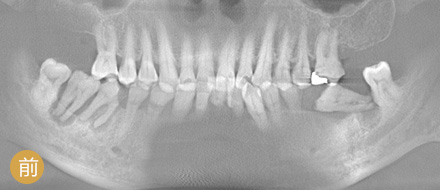

VS 传统种植牙 全数字化精确种牙

手术时间 平均1颗牙1小时 单颗牙5~10分钟

恢复周期 拔牙后3个月修养,需二次种植 即拔即种,即种即用

准确程度 依赖医生个人判断种植角度 外科导航系统定位,实时监控,避开血管神经

安全性 医生个人经验决定了种牙效果 神经、血管可见,导航全程定位,

种牙效果稳定可靠

功能行使 愈合周期略久,较难参与日常咀嚼 种牙后即可马上使用